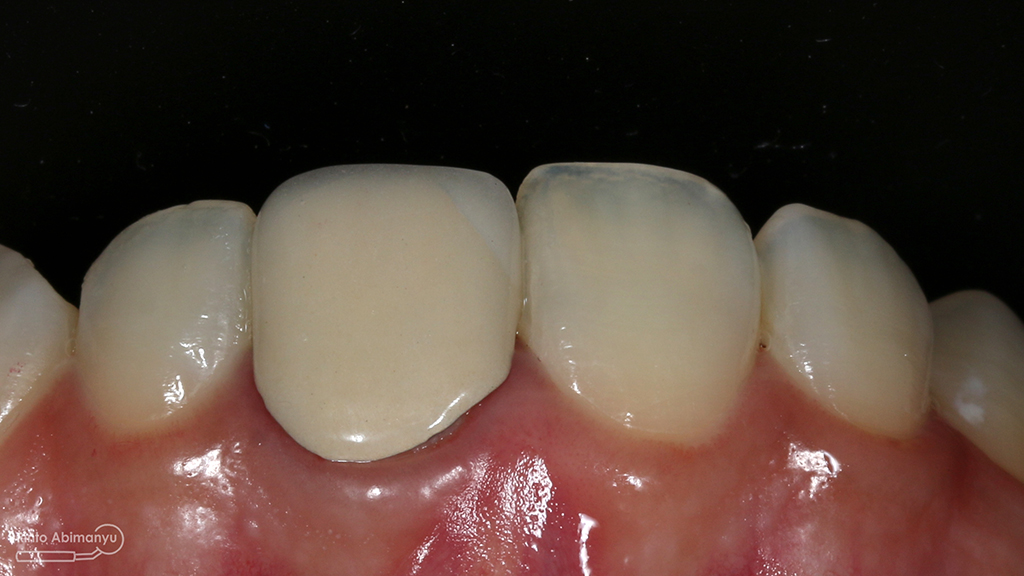

Begini kondisi klinis saat datang…

Foto klinis gigi-gigi anterior yang mengalami fraktur

ini hasil preparasi gigi-giginya…

Hasil preparasi tampak depan

Hasil preparasi tampak oklusal

Foto klinis setelah pemasangan crown